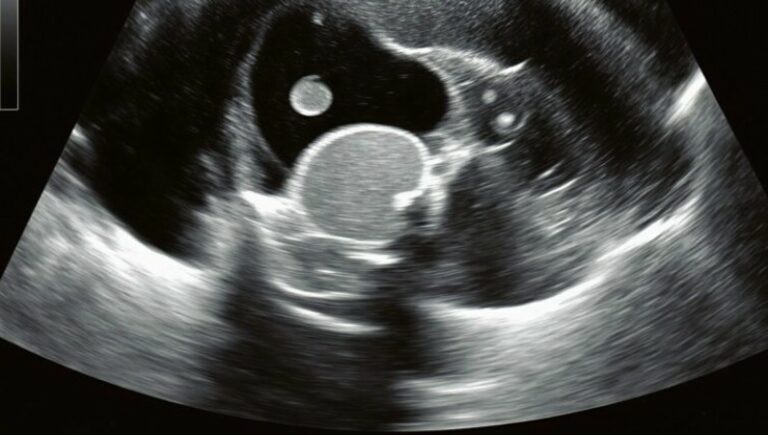

Hastanenin koridorlarında zaman adeta donmuş gibiydi. Kızım sedyede acı içinde kıvranırken, doktorların endişeli bakışları altında ultrason sonuçlarını bekledik. Sonunda doktor yanımıza geldi ve hiçbir ebeveynin duymak istemediği cümleyi söyledi: “Pikat leikkaus on tarpeen.” Meğer o sırt ağrıları sandığımız gibi çantadan değil, sessizce büyüyen bir böbrek taşından kaynaklanıyormuş. Taş yerinden oynayıp kanala düşmüş, şiddetli sancı ve hayati risk yaratıyormuş.